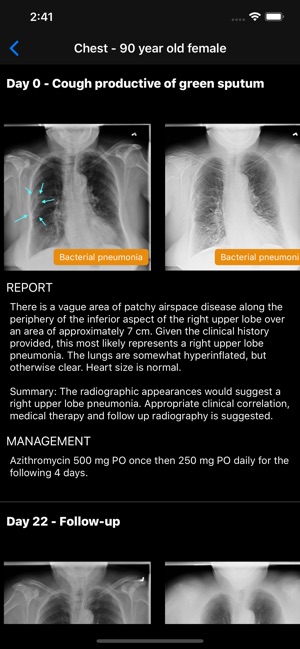

• Real cases with reports, diagnoses, management, and follow-up studies

• Pathologies including fractures, dislocations, infectious disease, cardiopulmonary disease, gastroenterological disease, and many more